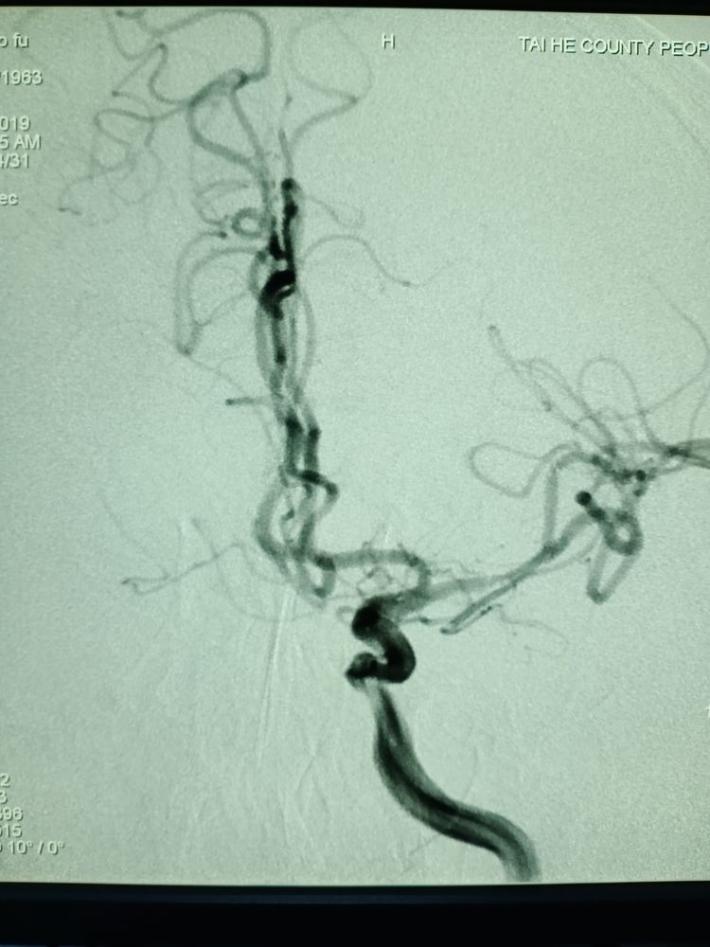

右侧颈总动脉造影提示:右侧颈内动脉颅内段慢性闭塞,非责任病变。

左侧椎动脉造影提示:右侧后交通动脉开放,后循环向前循环代偿供血。

取栓后五分钟,血流减慢,难以维持,左侧大脑中动脉M1段原位狭窄。

球囊扩张

球囊扩张后30分钟,重复造影,狭窄明显改善,前向血流TICI3级。